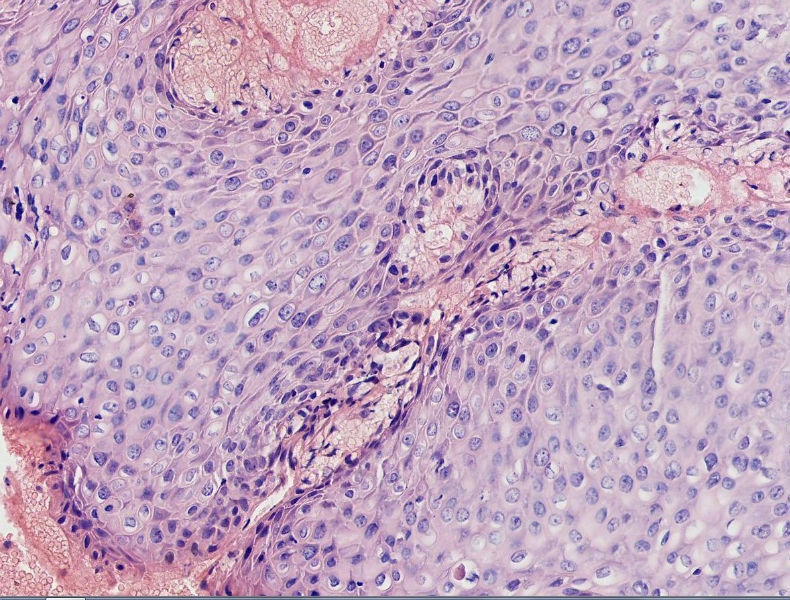

女45岁,宫颈口可见一突出物直径约0.5菜花状质脆

图4

细胞异型性不太大,考虑湿疣样增生

CIN3,伴湿疣感染

细胞异型不大,乳头状瘤。

乳头状的CIN,有平切,似乎有高级别的CIN,需除外癌。